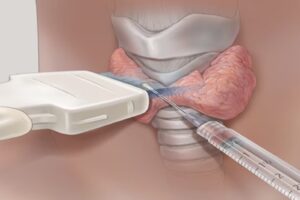

Οι αιματολογικές εξετάσεις για τις θυροειδικές ορμόνες συνήθως περιλαμβάνουν τη μέτρηση των επιπέδων θυροειδικών ορμόνων στο αίμα. Οι κύριες θυροειδικές ορμόνες που μετριούνται συνήθως είναι η θυροξίνη (T4) και η τριϊόδηθυρονίνη (T3). Επιπλέον, μερικές φορές μπορεί να μετρηθεί και η θυροστιμουλίνη (TSH), η οποία εκκρίνεται από το υποφυσικό και ελέγχει τη λειτουργία των θυροειδικών αδένων.

Οι αιματολογικές εξετάσεις για τις θυροειδικές ορμόνες συνήθως περιλαμβάνουν τη μέτρηση των επιπέδων θυροειδικών ορμόνων στο αίμα. Οι κύριες θυροειδικές ορμόνες που μετριούνται συνήθως είναι η θυροξίνη (T4) και η τριϊόδηθυρονίνη (T3). Επιπλέον, μερικές φορές μπορεί να μετρηθεί και η θυροστιμουλίνη (TSH), η οποία εκκρίνεται από το υποφυσικό και ελέγχει τη λειτουργία των θυροειδικών αδένων.